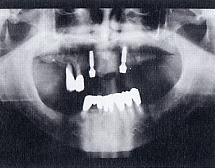

インプラント埋入後のレントゲン写真

![]()